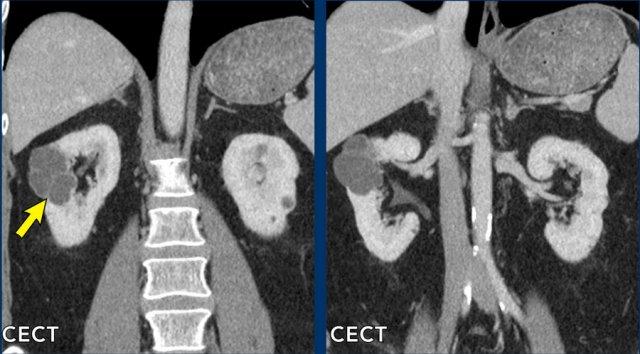

Tổn thương 1 (mũi tên vàng)

Quan sát thấy một tổn thương đồng nhất, giảm tỷ trọng ở mặt sau thận phải. Tổn thương này quá nhỏ để phân loại và được xếp vào nhóm Bosniak II.

Tổn thương 2 (mũi tên trắng)

Trên CT không tiêm thuốc cản quang (NECT), có một tổn thương tăng tỷ trọng ở thận trái với HU > 70, thông thường tương ứng với tổn thương Bosniak II (mũi tên trắng). CT có tiêm thuốc cản quang (CECT) trong pha tĩnh mạch cửa không cho thấy sự ngấm thuốc đáng kể nhưng có hình ảnh không đồng nhất.

Trường hợp này cần chụp thêm MRI để đánh giá bổ sung (xem hình ảnh tiếp theo).

MRI của cùng bệnh nhân.

Tổn thương giảm tín hiệu trên chuỗi xung T2W và tăng tín hiệu trên chuỗi xung T1W.

Không có ngấm thuốc tương phản từ trên chuỗi xung trừ (subtraction).

Trên MRI, tổn thương được xác nhận là Bosniak II.